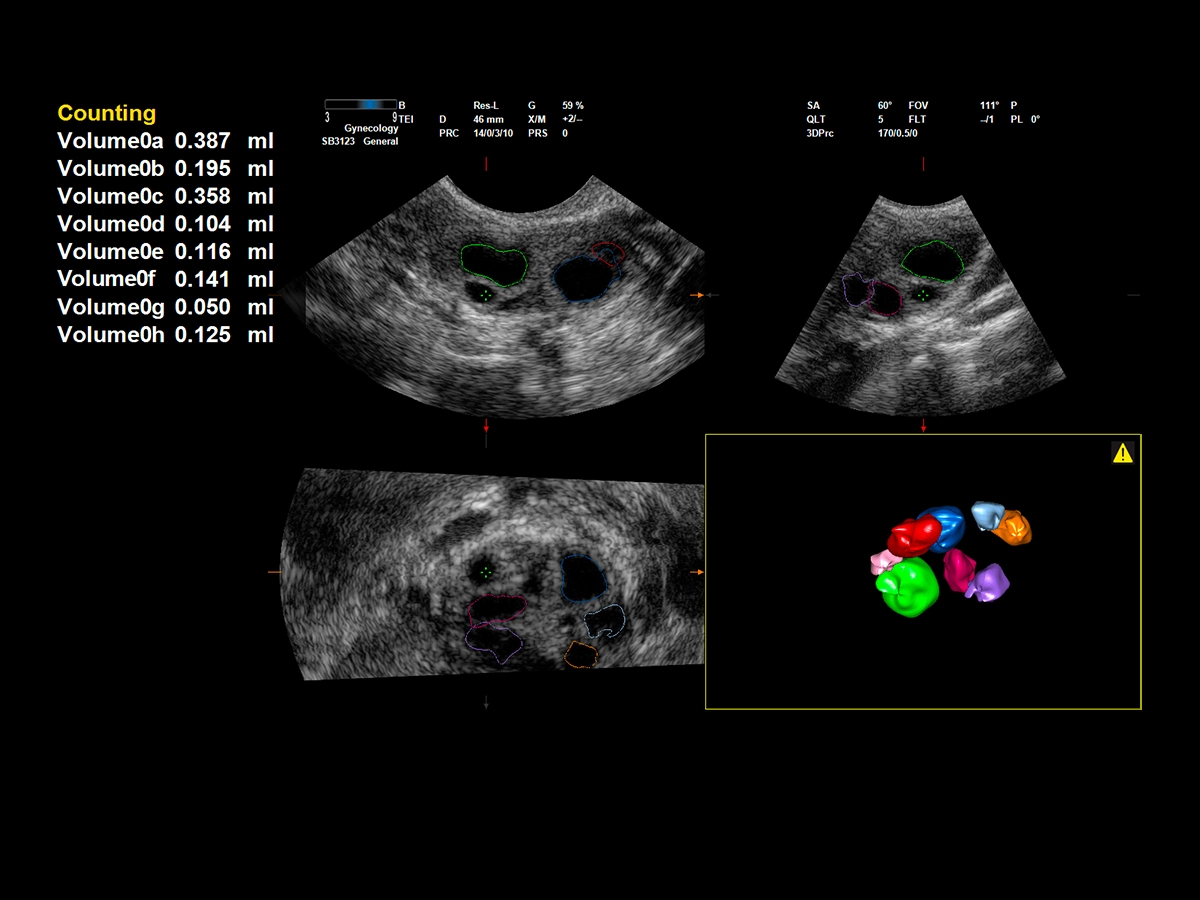

Ultrasound plays a significant role in the field of medically assisted procreation (MAP) and reproductive medicine. Follicle monitoring is one critical aspect in fertility management. XVRA is the innovative Esaote tool that automatically calculates follicle volume, thus helping in the identification of the best oocytes to be collected, to increase the chance of pregnancy.